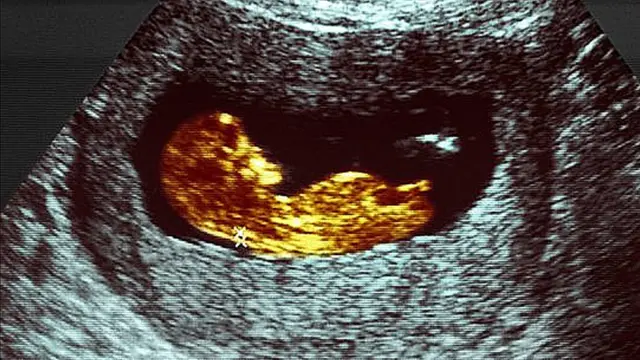

- 12 meses de gestación

El feto que fuiste fue creciendo dentro del vientre, acolchonado por el fluido amniótico.

A las 12 semanas, empezaste a tomar tragos de ese líquido.

Al principio del embarazo, este fluido era poco más que agua y sales de la sangre de tu mamá, pero a los 3 meses de tu gestación, ya contenía sus proteínas, carbohidratos y grasas, así como sustancias químicas con el sabor de la comida que ella estaba ingiriendo.

Como tus células gustativas continuaron desarrollándose, empezaste a distinguir lo dulce de lo amargo.

Y seguiste tomando más y más fluido amniótico a lo largo de la gestión, hasta que llegaste a beberte hasta 750 mililitros al día.